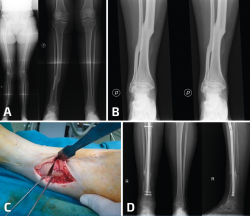

Figura 1. Paciente con genu varo ya operado por pie plano valgo con coalición tarsal y tobillo doloroso. A: se realizó una osteotomía varizante de calcáneo; B: la mejoría después de la cirugía del retropié fue insuficiente y se realizó una osteotomía valguizante de tibia proximal; C: imágenes radiológicas al año de la cirugía. El paciente se encontraba asintomático de su tobillo, que había mejorado también en apariencia radiológica.

La región diafisaria de la tibia también puede presentar una desaxación como consecuencia de una consolidación viciosa de una fractura de tibia. En este escenario, la artropatía del tobillo puede mejorar de manera muy llamativa con la corrección de la deformidad proximal (Figura 2).